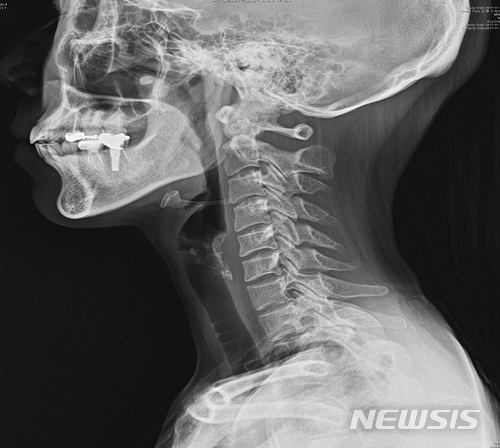

【서울=뉴시스】일자목.2018.02.25(제공=국민건강보험 일산병원)

기본적으로는 목부위 통증이 동반된 경우에서 X-ray 검사를 통해 목척추의 전만이 감소한 소견을 확인하게 되며 심한 경우에는 목척추가일자 모양을 넘어 후만 굴곡을 보이는 경우가 있다.